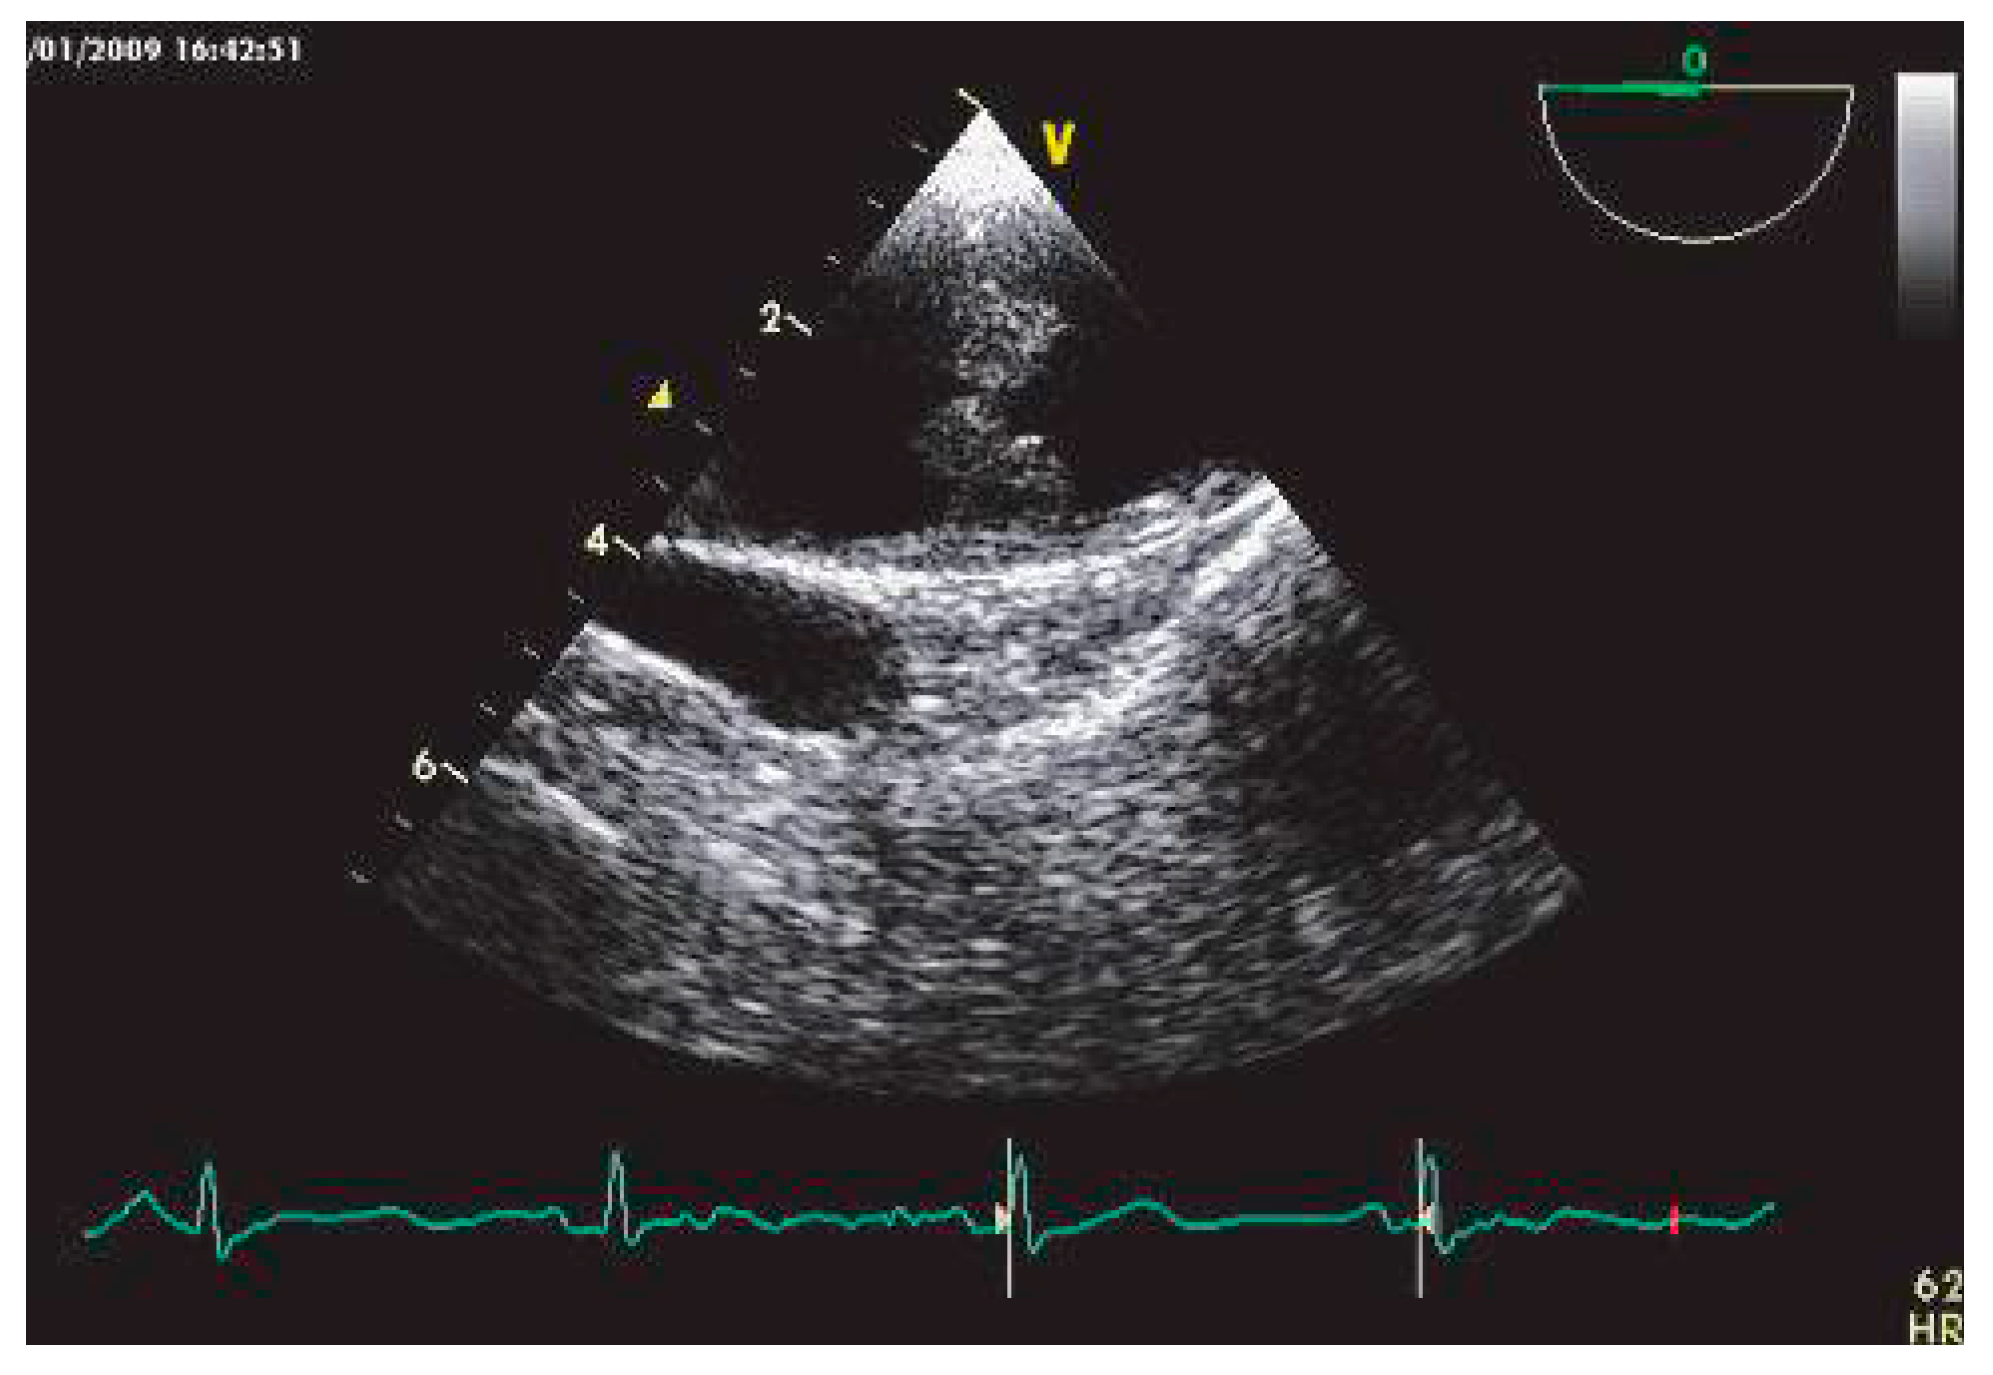

Thrombus et dysfonction systolique ventriculaire gauche ischémique et non ischémique

L’AIC complique un infarctus du myocarde (IDM) dans 2 à 4% des cas [27]. La thrombose ventriculaire gauche (VG) est habituellement précoce, survenant dans la première semaine suivant l’IDM. Le siège électif est l’apex VG, en regard d’une zone akinétique ou dyskinétique, ou au sein d’un anévrisme (Figure 2). Cette localisation élective explique la performance diagnostique élevée d’ETT. La présence d’un thrombus VG à la phase aiguë d’un IDM multiplie par 5 le risque embolique [28].

Figure 2. Thrombus mobile du VG chez un patient hospitalisé pour AIC et porteur d’une séquelle apicale, visualisé en ETT par la fenêtre apicale.